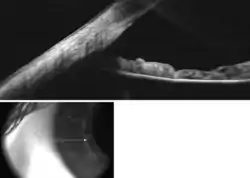

Figure 1. Calculating EZ ratio.

Figure 2. Different anterior chamber depths as seen from the lateral perpendicular (profile) view. The more forward the pupil is, the shallower the anterior chamber. In the leftmost photo, the pupil is relatively posterior (set back), indicating an EZ ratio of < 0.5 and an anterior chamber deeper than 2.5 mm. In the middle photo, the pupil is midway between the sclera posteriorly and the cornea anteriorly, indicating an EZ ratio of 0.5, and a medium chamber depth of about 2.5 mm. In the rightmost photo, the pupil is very anterior (forward), indicating an EZ ratio of more than 0.5 and a shallow anterior chamber of less than 2.5 mm.